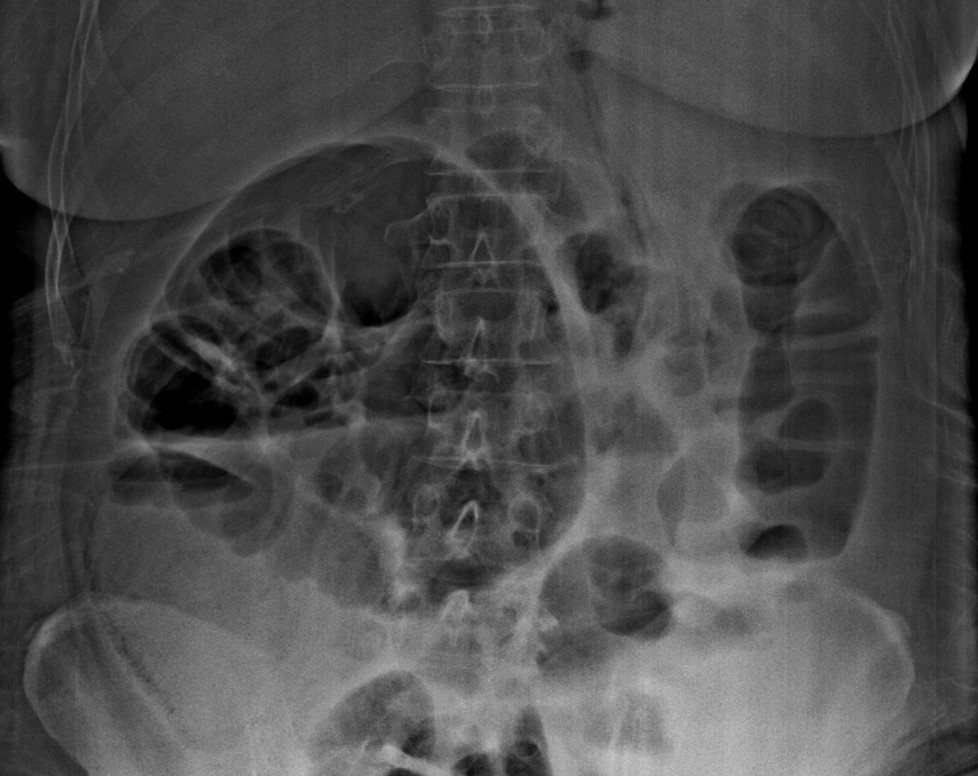

What is the positive finding in the plain abdominal radiograph?

Answer : A. Large bowel dilatation

Answer : C. Air in the bowel wall or pneumatosis intestinalis

This case show curvilinear gas in the cecal wall